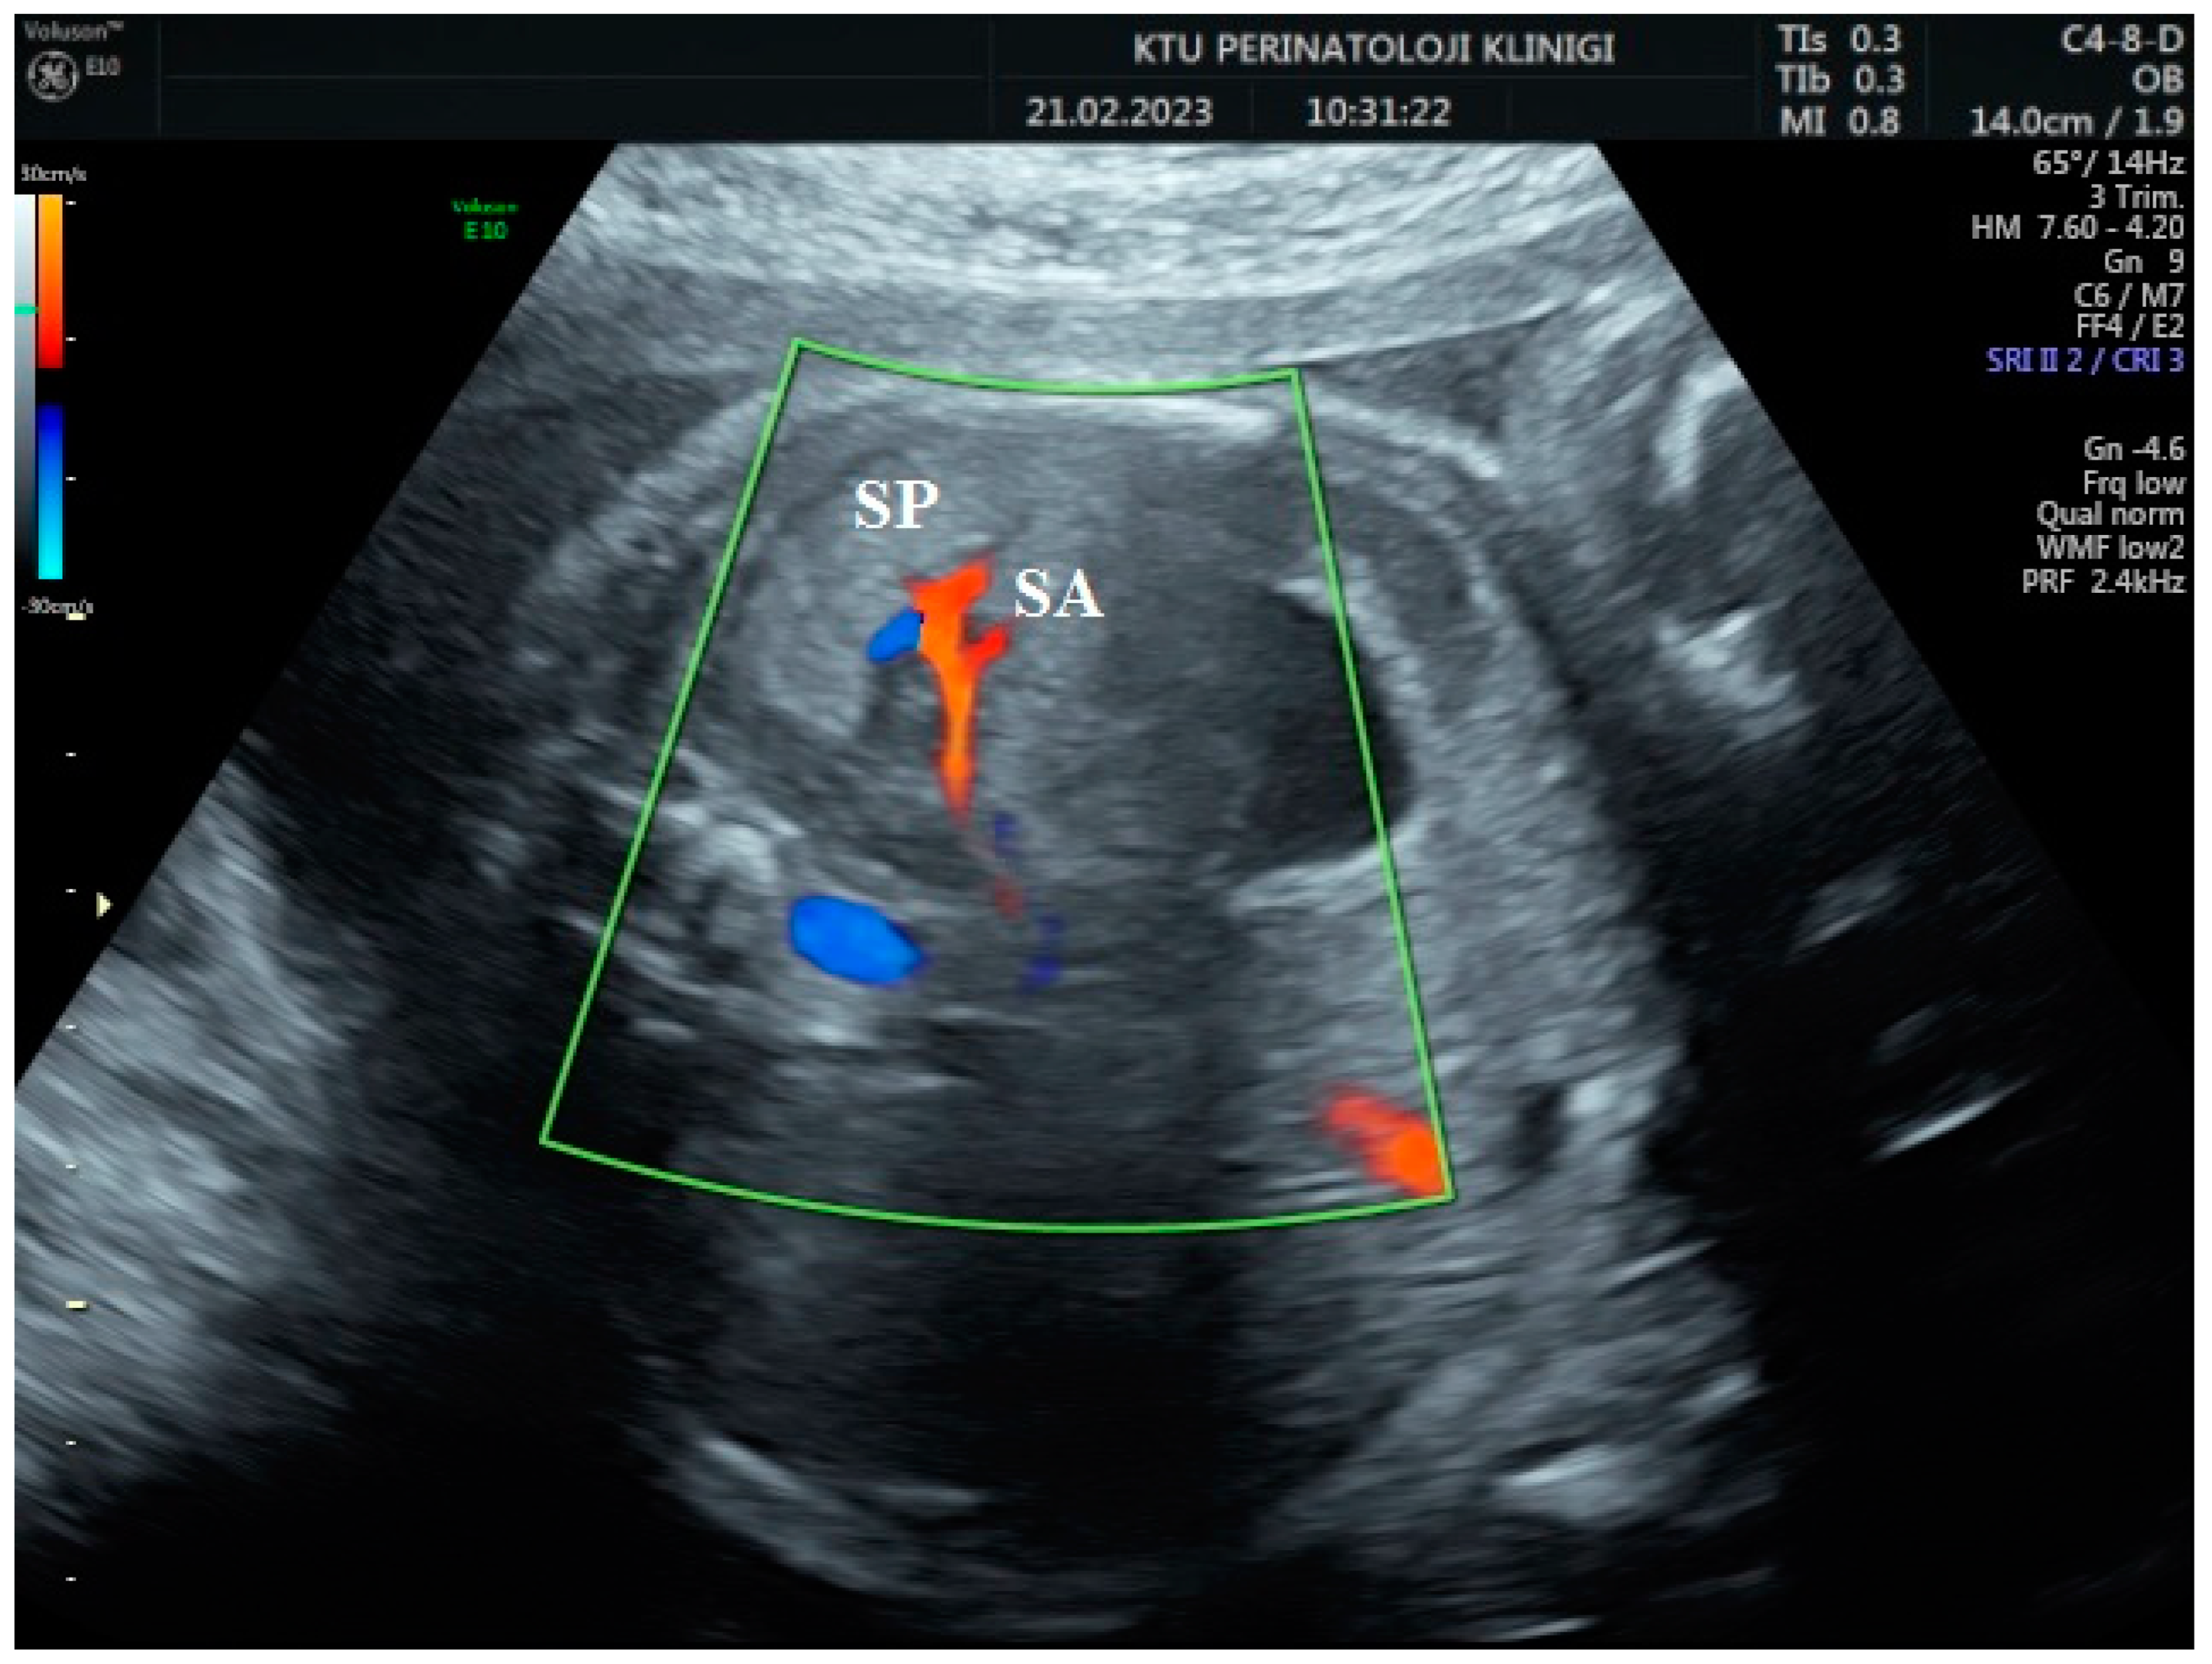

During the Doppler assessment, the patient was positioned on the examination table in a supine posture. It was measured when the fetus was inactive. A standard AC axial section view was obtained. The stomach pocket was visualized. A color Doppler was placed on the upper part of the stomach pocket, and the splenic artery was visualized at the entrance to the spleen. Later, it was observed that the trace progressed towards the truncus, celiacus, and abdominal aorta. A color Doppler was placed at the entrance to the spleen with a 0-degree insomination angle without the splenic artery entering the spleen. Fetal splenic artery Doppler parameters such as peak systolic velocity (PSV), pulsatility index (PI), resistivity index (RI), and end-diastolic velocity (EDV) were measured in all cases (Figure 1, Figure 2 and Figure 3). Following fetal splenic artery imaging, the vessel diameter was measured from the area directly in the middle. The vessel measurement was made from outside to outside, and the insomination angle was adjusted to be <30 degrees.

Figure 1. Two-dimensional ultrasonographic imaging of the 30-week-old fetus shows the fetal spleen (SP) and splenic artery (SA).